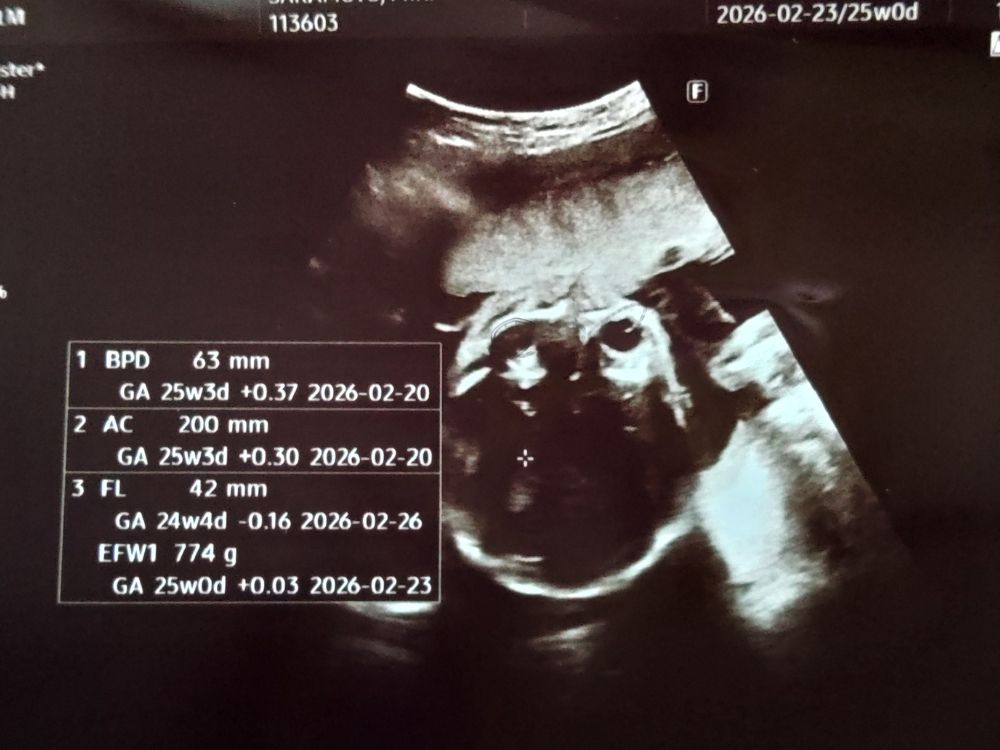

25wの妊婦健診。赤ちゃんは順調に成長!

今回は助産師さんのエコーのみ。順調で一安心

今回の25w健診は、特に問題がなかったため

助産師さんによるエコーのみの診察でした。

赤ちゃんの推定体重も774gと週数どおりで、とても元気。

大きく手足を動かしていて、画面越しに成長を感じられて嬉しくなりました。

25wの健診は助産師さんのエコーのみで、赤ちゃんが順調なことがわかり安心しました。